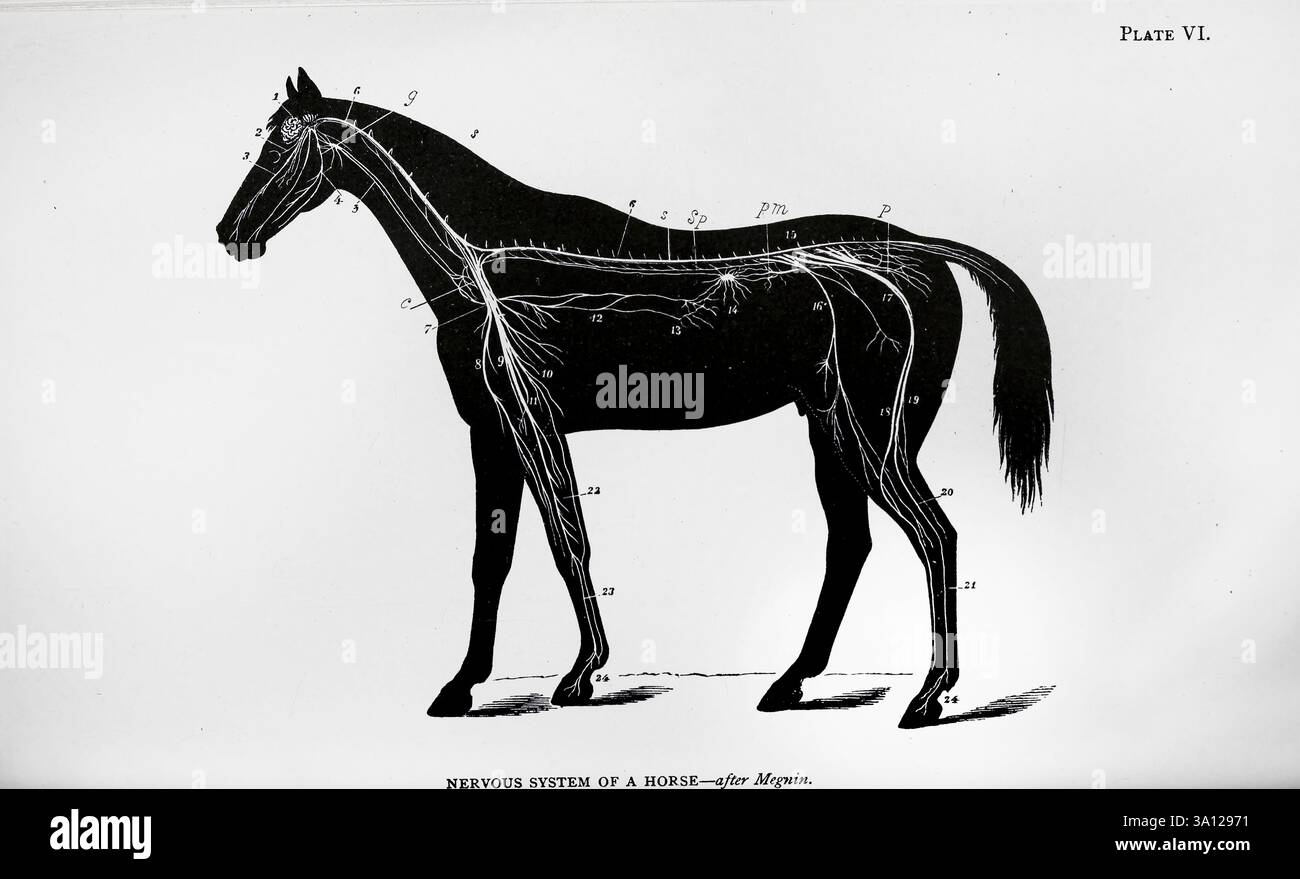

Système nerveux du cheval. ; 1. Cerveau. ; 2. Nerf optique. ; 'S. nerf maxillaire supérieur (5ème). ; 4. Nerf maxillaire inférieur (5ème). ; 5. Nerf pneumo-gastrique. ; 6. Medulla oblongata. ; 7. Plexus brachial droit ; 8. Nerf musculo-cutané. ; 9. Nerf médian. ; 10. Nerf radial. ; 11. Nerf cubital. ; 12. Nerf pneumo-gastrique. ; 13. Plexus solaire. ; 14. Ganglion semi-lunaire. ; 15. Plexus lombo-sacré. ; 16. Nerf crural antérieur. ; 17. Grand nerf sciatique. ; 18. Nerf poplité externe. ; 19. Nerf saphénique externe. ; 20. Nerf tibial. ; 21. Nerf métatarsien. ; 22. Portion radiale du nerf médian. ; 23. Métacarpien n Banque D'Imageshttps://www.alamyimages.fr/image-license-details/?v=1https://www.alamyimages.fr/systeme-nerveux-du-cheval-1-cerveau-2-nerf-optique-s-nerf-maxillaire-superieur-5eme-4-nerf-maxillaire-inferieur-5eme-5-nerf-pneumo-gastrique-6-medulla-oblongata-7-plexus-brachial-droit-8-nerf-musculo-cutane-9-nerf-median-10-nerf-radial-11-nerf-cubital-12-nerf-pneumo-gastrique-13-plexus-solaire-14-ganglion-semi-lunaire-15-plexus-lombo-sacre-16-nerf-crural-anterieur-17-grand-nerf-sciatique-18-nerf-poplite-externe-19-nerf-saphenique-externe-20-nerf-tibial-21-nerf-metatarsien-22-portion-radiale-du-nerf-median-23-metacarpien-n-image654659797.html

Système nerveux du cheval. ; 1. Cerveau. ; 2. Nerf optique. ; 'S. nerf maxillaire supérieur (5ème). ; 4. Nerf maxillaire inférieur (5ème). ; 5. Nerf pneumo-gastrique. ; 6. Medulla oblongata. ; 7. Plexus brachial droit ; 8. Nerf musculo-cutané. ; 9. Nerf médian. ; 10. Nerf radial. ; 11. Nerf cubital. ; 12. Nerf pneumo-gastrique. ; 13. Plexus solaire. ; 14. Ganglion semi-lunaire. ; 15. Plexus lombo-sacré. ; 16. Nerf crural antérieur. ; 17. Grand nerf sciatique. ; 18. Nerf poplité externe. ; 19. Nerf saphénique externe. ; 20. Nerf tibial. ; 21. Nerf métatarsien. ; 22. Portion radiale du nerf médian. ; 23. Métacarpien n Banque D'Imageshttps://www.alamyimages.fr/image-license-details/?v=1https://www.alamyimages.fr/systeme-nerveux-du-cheval-1-cerveau-2-nerf-optique-s-nerf-maxillaire-superieur-5eme-4-nerf-maxillaire-inferieur-5eme-5-nerf-pneumo-gastrique-6-medulla-oblongata-7-plexus-brachial-droit-8-nerf-musculo-cutane-9-nerf-median-10-nerf-radial-11-nerf-cubital-12-nerf-pneumo-gastrique-13-plexus-solaire-14-ganglion-semi-lunaire-15-plexus-lombo-sacre-16-nerf-crural-anterieur-17-grand-nerf-sciatique-18-nerf-poplite-externe-19-nerf-saphenique-externe-20-nerf-tibial-21-nerf-metatarsien-22-portion-radiale-du-nerf-median-23-metacarpien-n-image654659797.htmlRM3A12971–Système nerveux du cheval. ; 1. Cerveau. ; 2. Nerf optique. ; 'S. nerf maxillaire supérieur (5ème). ; 4. Nerf maxillaire inférieur (5ème). ; 5. Nerf pneumo-gastrique. ; 6. Medulla oblongata. ; 7. Plexus brachial droit ; 8. Nerf musculo-cutané. ; 9. Nerf médian. ; 10. Nerf radial. ; 11. Nerf cubital. ; 12. Nerf pneumo-gastrique. ; 13. Plexus solaire. ; 14. Ganglion semi-lunaire. ; 15. Plexus lombo-sacré. ; 16. Nerf crural antérieur. ; 17. Grand nerf sciatique. ; 18. Nerf poplité externe. ; 19. Nerf saphénique externe. ; 20. Nerf tibial. ; 21. Nerf métatarsien. ; 22. Portion radiale du nerf médian. ; 23. Métacarpien n